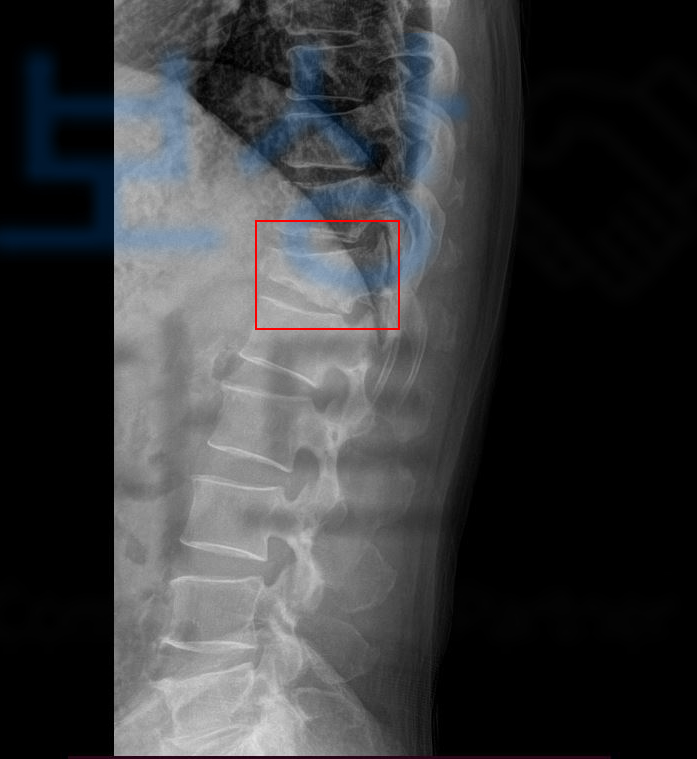

아프지 않고, 뼈가 잘 유합되었어도 척추골절의 특성상 원통 모양의 척추체가 무너지는 형태로 골절되기 때문에 척추가 기본적으로 가지고 있는 각도가 변형되기 시작하고 이러한 이유 등으로 보험약관상 “장해”에 해당될 수 있는 거죠.

환자의 흉추12번 척추골절 장해는 무려 뚜렷한 기형 30% 영구 장해에 해당하였습니다. 이후 흉추 12번 척추골절 장해에 대한 적정성을 증명하기 위해 손해 사정서 및 증빙자료를 각 보험사에 송부하였고 보험사에서도 조사관을 배정하여 내부 자문 및 의료자문을 시행하며 환자의 장해에 대한 면밀한 조사를 진행하였습니다.